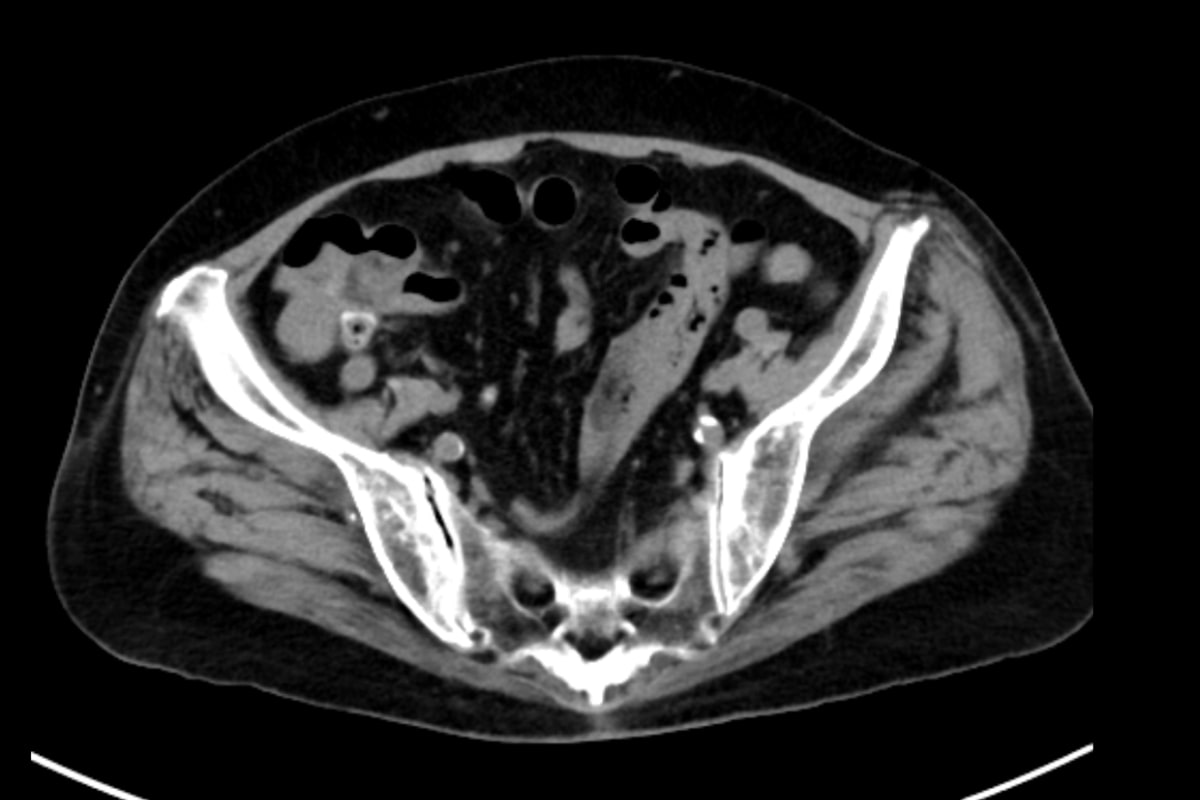

70歳代、女性、51kg、上行結腸憩室出血

複数回の結腸憩室出血での入院歴がある方。今回も多量の血便があり、入院となった。出血源の検索目的に造影CTが施行された。

血便があり、当院消化器内科に入院となった。第3病日に下部消化管内視鏡を行うも出血源は不明であった。第4病日に再度血便があり、造影CTを施行すると上行結腸憩室からの活動性出血を認めたため、速やかに緊急TAEを施行した。血管造影で回結腸動脈の分枝からextravasationを認め、責任動脈をコイル塞栓した。術後、再出血、Hb値の低下を認めず、第13病日に退院となった。

消化管出血では出血源を迅速かつ正確に同定することが診療上、不可欠である。内視鏡は有用であるものの、腸管の前処置を要し、観察に時間を要する他、出血が間欠的であれば診断が困難となる場合がある。これに対して造影CTは、非侵襲的かつ短時間で活動性出血の有無と局在を明確に描出できる。活動性出血があれば、動脈相から腸管内への造影剤の漏出を認め、静脈相や遅延相ではその造影剤漏出の拡大を確認することで、客観的に活動性出血を診断できる。さらに、造影CTで得られた情報に基づき責任血管を同定することで、後続の血管造影検査の効率が高まり、速やかに経カテーテル的動脈塞栓術(TAE)へと移行できる。当院では、造影CTで活動性出血が確認された結腸憩室出血に対して速やかにTAEを施行しており、その成功率向上に寄与している。一方で、出血が間欠的または少量の場合には描出が難しく、検査のタイミングによって診断能が左右されるという限界もある。それでも、結腸憩室出血において造影CTは診断と治療方針をつなぐ、重要な検査として位置付けられる。

CT技術や撮像プロトコル設定について

本症例ではPhoton Counting CT(PCCT)を用いた。PCCTは従来型CTに比べ空間分解能とコントラスト分解能が高く、少量の造影剤でも高精細な画像を得られることが特徴である。これにより微細なextravasationやそれに連続する責任動脈の描出が可能となり、診断精度を大きく高める。

撮像プロトコルは活動性出血が疑われる場合、動脈相と平衡相の2相を基本としている。ボーラストラッキングを用いて造影剤到達を正確に把握し、動脈相でextravasationを描出し、平衡相で造影剤漏出の拡大を確認することで、出血の有無と局在を診断している。

造影剤はイオプロミド370を使用し、25秒間で投与、投与速度は24mgI/kg/secとした。撮像はPrep直後に動脈相を、続いて100秒後に平衡相を撮像する設定とし、効率的に活動性出血の有無を把握できるよう工夫している。

PCCTによる高精細な画像はextravasationの検出にとどまらず、責任血管を描出することで標的血管の特定を容易にする。その結果、血管造影での探索時間が短縮され、経カテーテル動脈塞栓術(TAE)の迅速かつ確実な施行につながり、手技の成功率と効率を高めている。